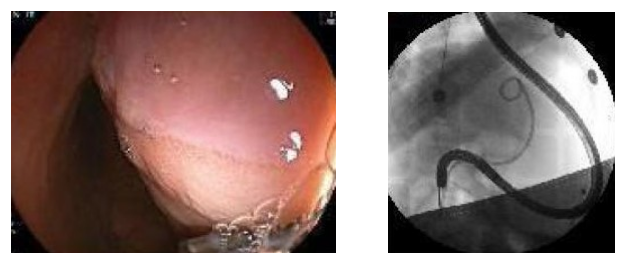

左:术中内镜下巨大囊肿压迫胃壁 右:术中放置引流管

在麻醉科的保驾护航下,消化科黄永辉主任医师为夏夏进行了超声引导下经胃壁穿刺引流,并放置了引流管,夏夏的内镜手术十分顺利。手术后她的肚子逐渐缩小,一直偏高的淀粉酶和脂肪酶也很快降至了正常水平。